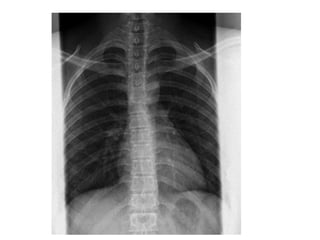

INCIDÊNCIAS DO TÓRAX

•1. Póstero-anterior: evitar a magnificação do coração e

possibilita o posicionamento dos ombros de tal forma que a

escápula fique fora do filme.

•2. Ântero-posterior: crianças pequenas e pacientes

acamados devido a dificuldade de posicionamento.

•3. Perfil: Usa-se perfil esquerdo para evitar magnificação do

coração. Sempre solicitada com a PA.

IDENTIFICAÇÃO DA RADIOGRAFIA

PA

Usa-se incidência PA

devido a localização

anatômica do coração.

Quanto mais perto do filme

menor a magnificação e

maior nitidez.

ESTRUTURAS MAIS

DEMONSTRADAS:

Pulmões, coração.

Usa-se o perfil com o

lado esquerdo próximo

do filme para evitar

que o coração seja

ampliado.